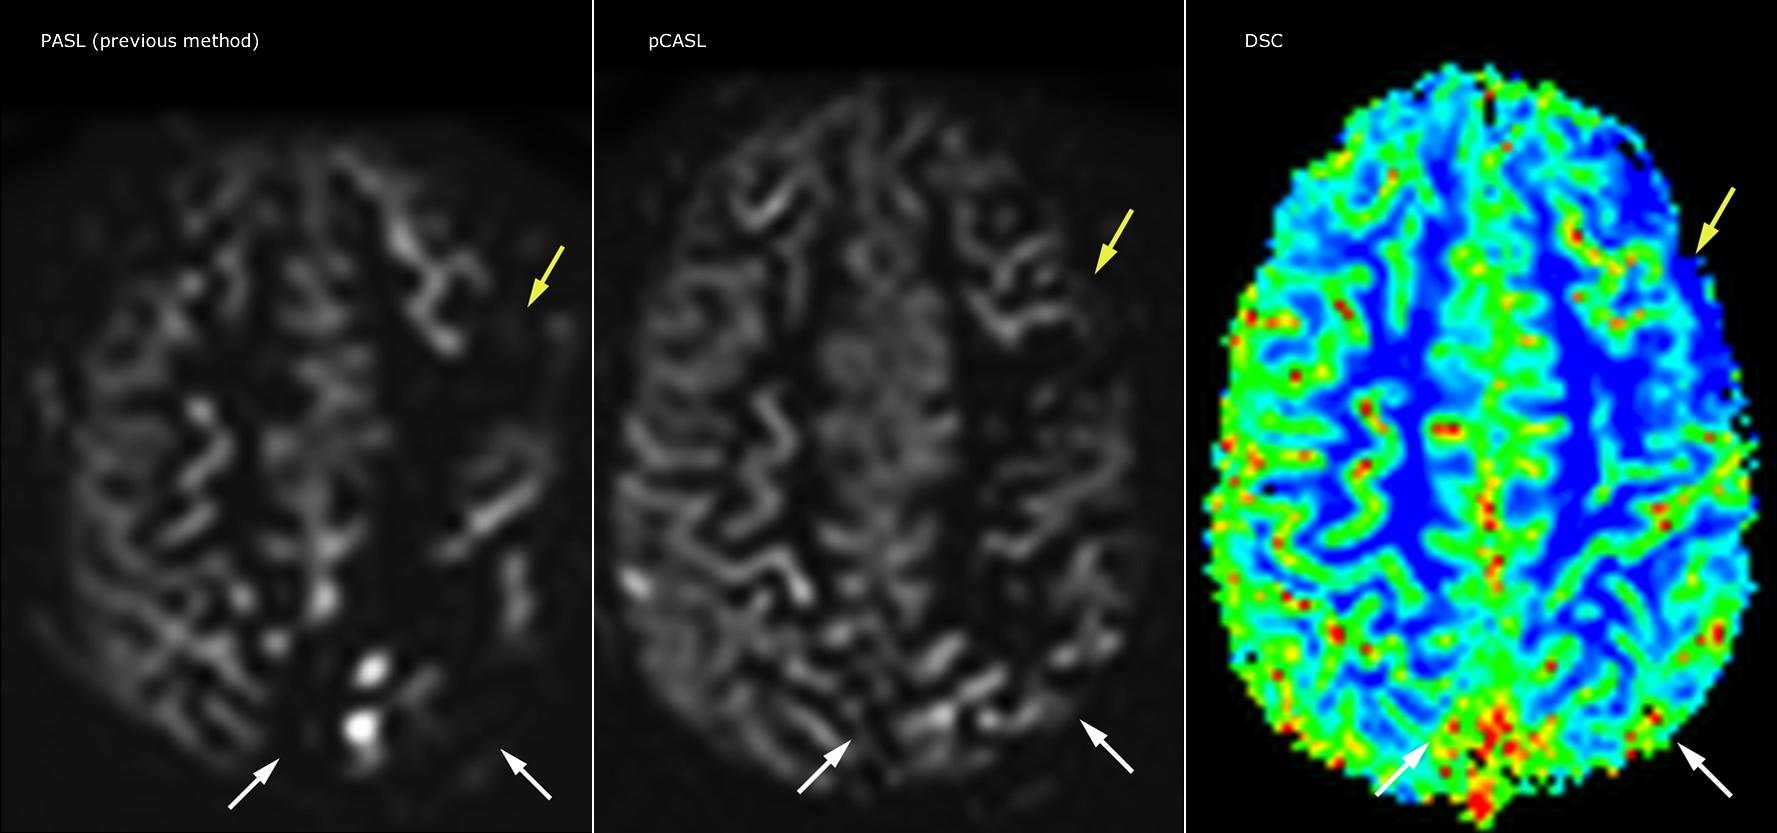

Philips mDIXON TSE is a two-point DIXON technique that separates water and fat signals, for time-efficient fat-free imaging, even in challenging neuro anatomy. “mDIXON TSE has been one of the most significant improvements in imaging sequences that we have utilized to date at PCH,” says Dr. Miller. “Its multi-parametric acquisition allows us to obtain fat suppressed images and equivalent non-fat suppressed T2 images all in the same sequence. In addition, prior methods of fat suppression could be artifactually corrupted by poor patient anatomy or poor operator application, but with mDIXON we now have a robust and reliable method of fat suppression.” Fat saturation is historically challenging at the ends of fields of view, especially in total spine imaging and in difficult patient anatomy such as the lower regions of the neck. “Due to the unique fat suppression capabilities of mDIXON, however, these challenges no long apply,” says Dr. Miller. “We routinely obtain homogeneous fat suppression under virtually all conditions. It has also led to some efficiencies by not having to repeat sequences because of that technical failure.”

“mDIXON TSE has increased our diagnostic confidence in ruling in or ruling out abnormalities in which fat suppression is critical to diagnosis, such as metastatic disease or osseous abnormalities.”

“mDIXON TSE is most useful in patients with lesions or abnormalities in the soft tissues such as the face and neck, and for patients with contrast enhancing abnormalities that are mostly visible with fat suppression,” says Dr. Miller. “All our spine imaging now routinely contains mDIXON water-only T2 images, and this allows us to identify pathology that may be obscured by non-fat suppressed imaging such as injuries of the bone. And it’s not necessary to obtain additional standard TSE T2 images because the in-phase mDIXON images are equivalent to standard TSE T2 images.”